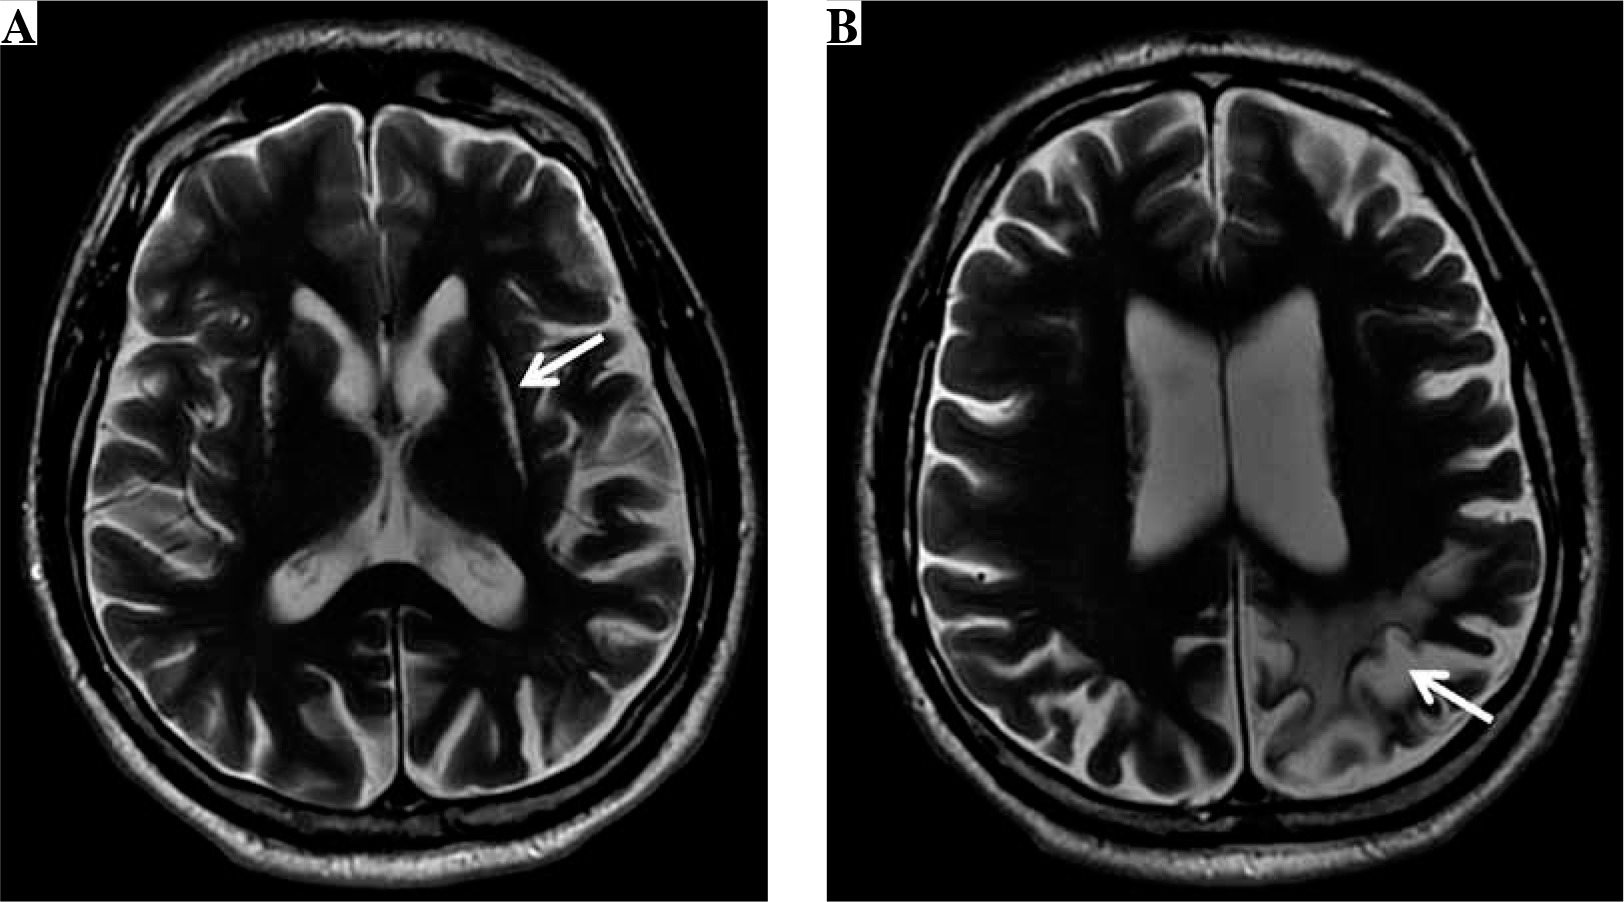

Two years after the cerebral vascular event resulting from wasp stings, the neurological examination of our patient revealed slight left hemiparesis with discrete spasticity of the lower limbs and with an extensor plantar response. The follow-up MR examination (Fig. 2) showed chronic external watershed ischemic lesions in the right hemisphere between the anterior and middle cerebral arteries and between the middle and posterior cerebral arteries. Moreover, there were chronic internal watershed lesions between the lenticulostriate and middle cerebral artery. Additionally, MR examination revealed moderate cortical and subcortical atrophy in this area.

Fig. 2

The brain magnetic resonance (MR) examination, axial (A) and sagittal (B) T2-weighted images reveal chronic external watershed ischemic lesions (black arrows) in the right hemisphere between the anterior and middle cerebral arteries and between the middle and posterior cerebral arteries (A). Moreover, there are chronic internal watershed lesions (white arrows) between the lenticulostriate and middle cerebral arteries